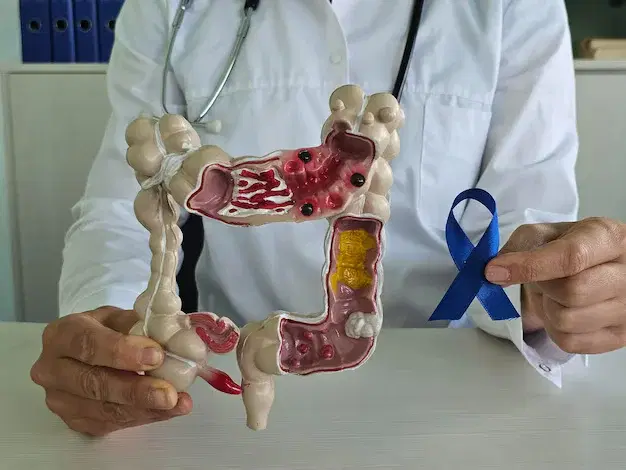

Laparoscopic Colon Cancer Surgery in Vijayawada

Laparoscopic colon cancer surgery is a minimally invasive procedure used to remove cancerous sections of the colon through small incisions. At Vijayawada Gastro Centre, our expert surgical team uses high-definition laparoscopic technology to ensure precise tumor removal, less pain, and faster recovery. This advanced approach reduces blood loss, minimizes scarring, and allows patients to return to daily activities sooner. We provide comprehensive care, including accurate diagnosis, staging, and personalized treatment planning. With modern facilities and experienced specialists, we offer safe, effective, and compassionate colon cancer surgery for patients in Vijayawada.